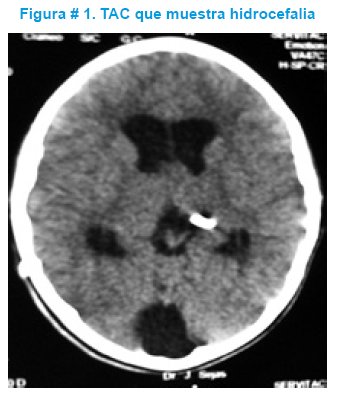

Los exámenes de laboratorio de rutina fueron normales. La TAC simple de cráneo informó hidrocefalia aguda severa, la misma que fue resuelta por una derivación ventrículo peritoneal, con evolución posterior favorable y fue dado de alta al 5to día post operatorio. Ver figura # 1.